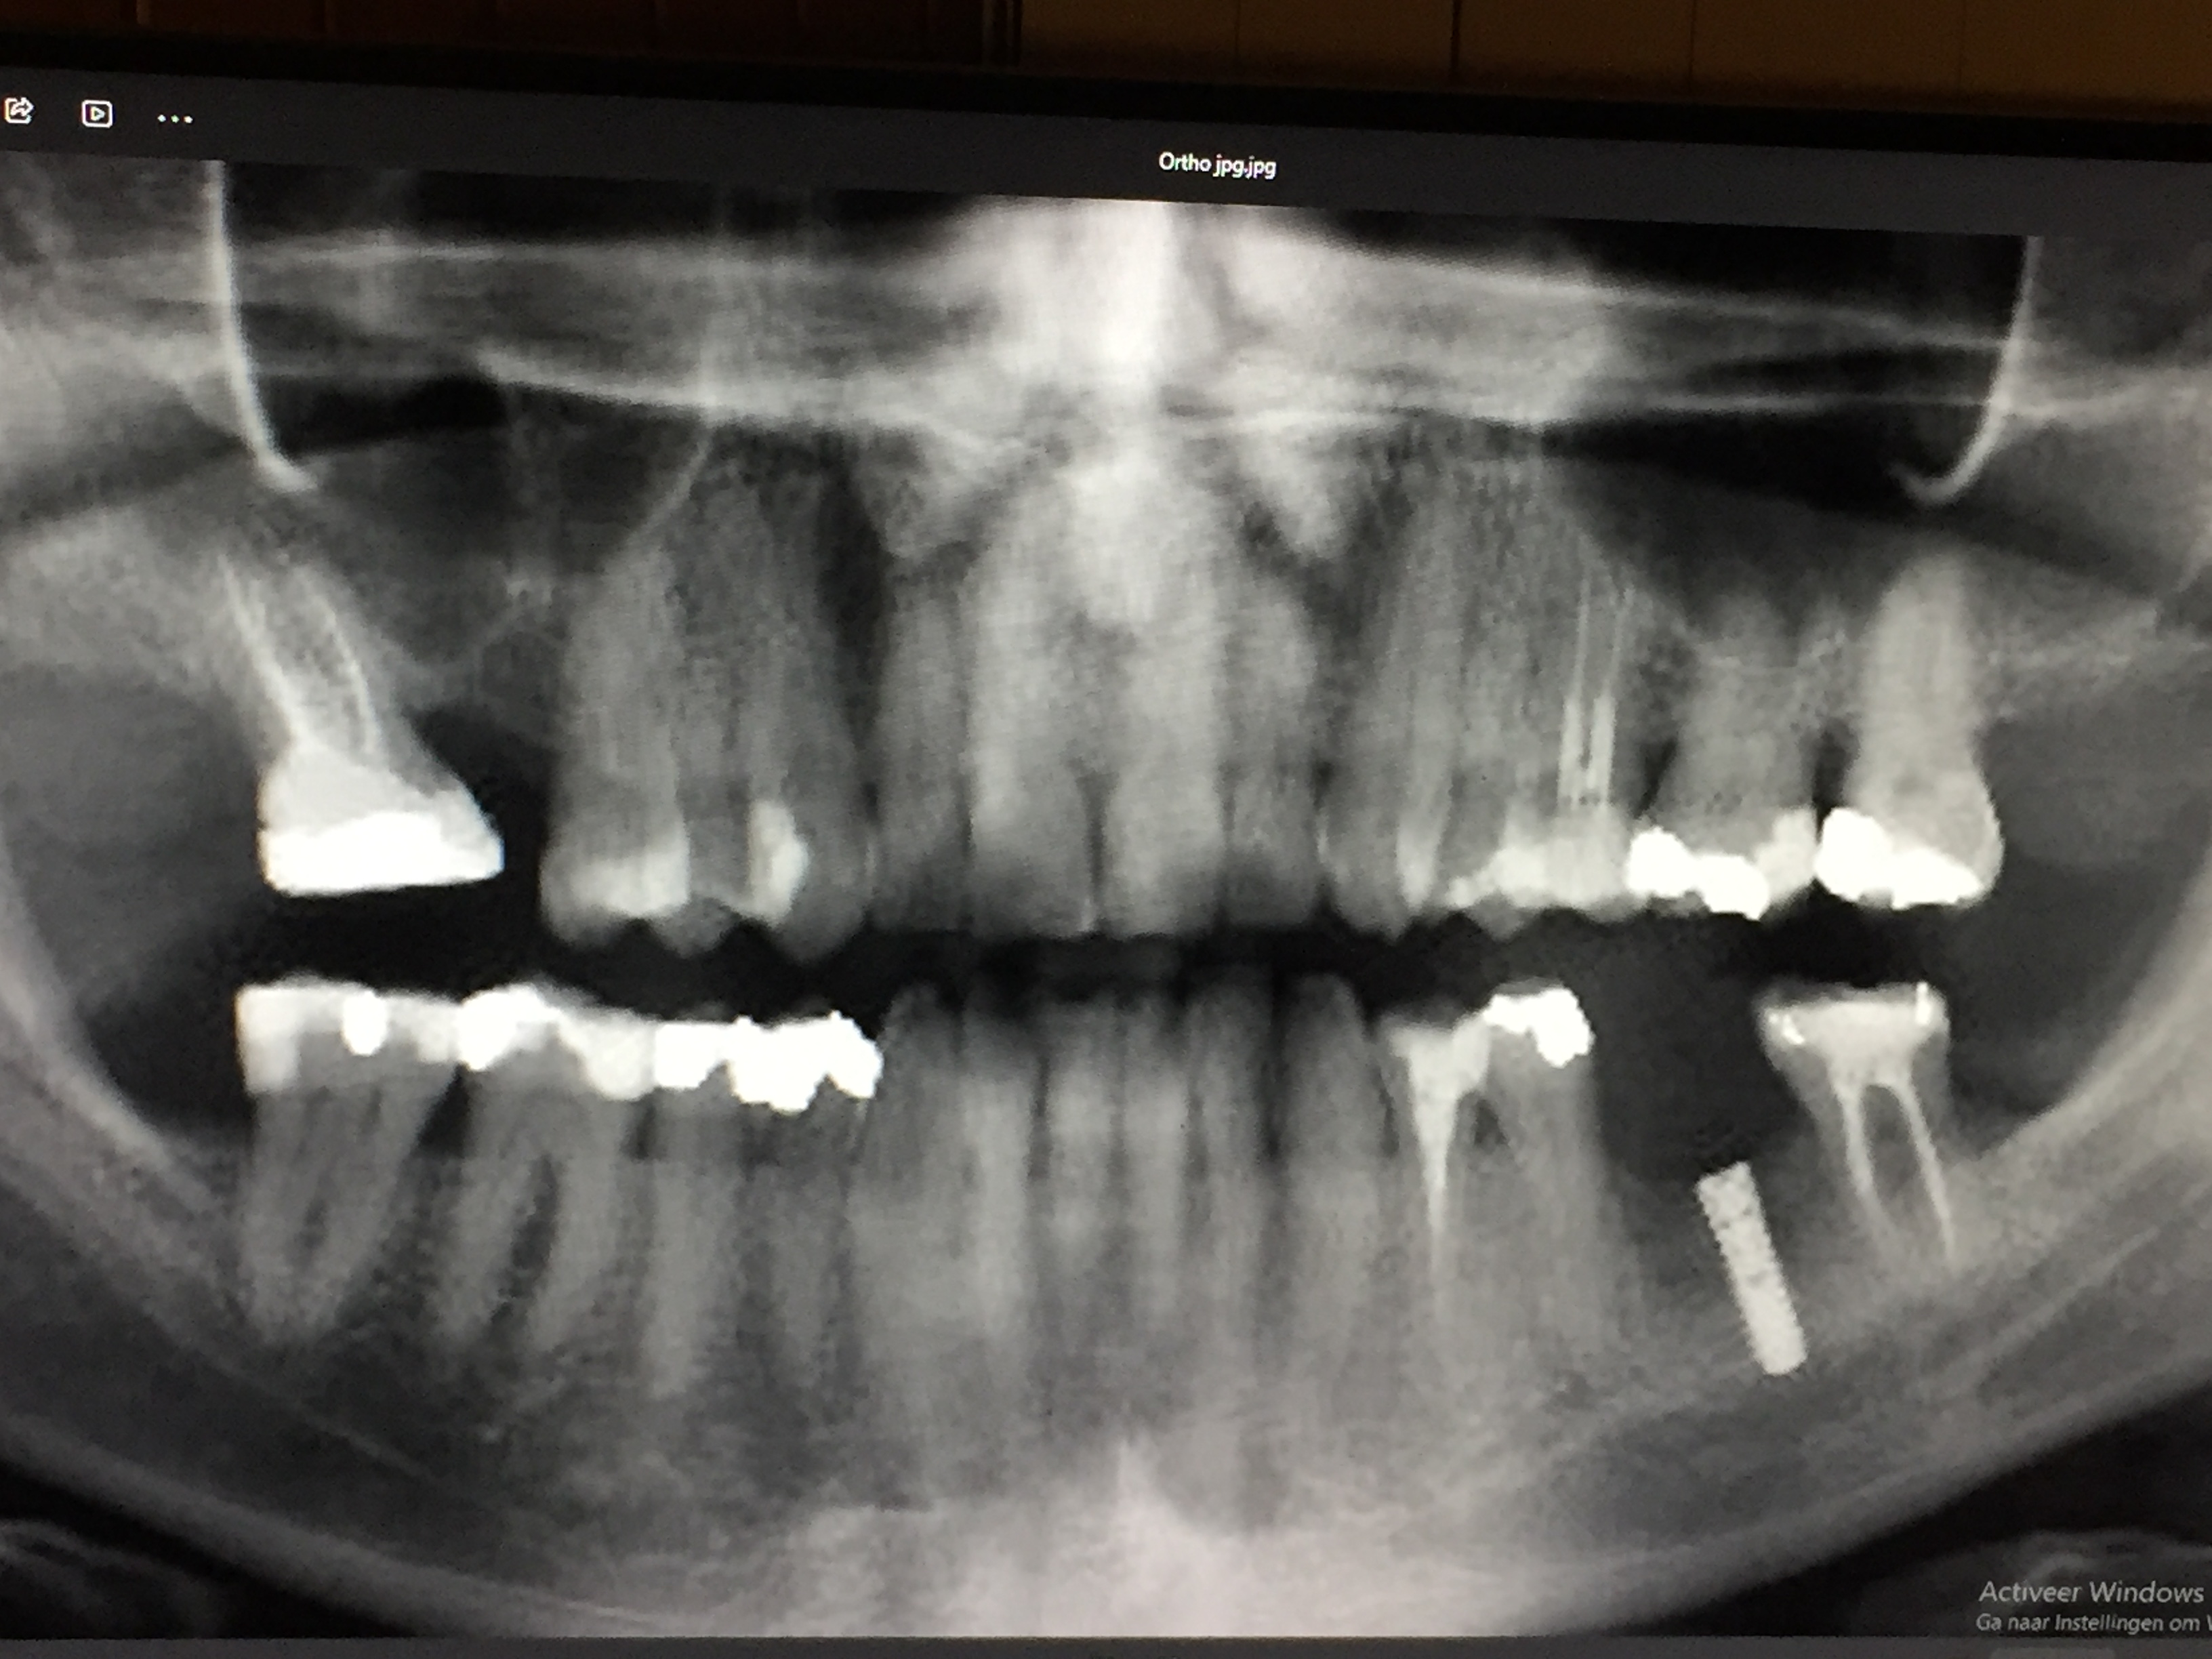

ik heb even een foto erbij voor Tandarts Richard .wat kunt u concluderen aan de hand van deze foto?

Tandarts_Richa…

idd lijkt op wortel resorptie. Element is helaas verloren. Oppassen voor mogelijke Antrum perforatie ( verbinding met neusholte) met verwijderen aangezien bot erg dun lijkt. Weet niet hoe de rest v h gebit eruit ziet.. maar nadenken over vervanging.

Dit is voor mij over duidelijk...sorry. Helaas waarschuwt het lichaam niet altijd gelijk als er iets mis is.

Met nadenken over vervanging bedoel ik ..hoe gaat u de verloren kauwfunctie opvangen...de mogelijkheden afhankelijk v rest gebit. Maak een uitgebreid behandel/stappen plan voor de toekomst v uw gebit/kauwvermogen. Laat een panorama foto maken. Daar staan alle wortelpunten op. Bij twijfel nog extra kleine foto. ( hier posten zonder naam vermelding geef ik mijn mening)

Als ik de laatste foto bekijk dan zijn er een paar zaken die ik mij afvraag.

- Is er een totaal plan gemaakt voor herstel v h gebit. Beginnend bij de ophanging...uw bot verlies.

- Als een wkb gedaan wordt adviseer ik altijd een knobbel overkappend vulling of een kroon waarbij een kroon vaak mijn voorkeur heeft.

- Er zijn vele grote vullingen... zijn daar adviezen voor kronen gegeven.

- Bij de 36 is een advies impl gegeven om de verloren gegane ruimte op te vullen... hoe zit dat rechts boven..welk advies.

- resorptie (intern of extern) is niet altijd te voorkomen dus als daar een kroon was geplaatst was het misschien toch gebeurd,,,of was er een lekkage die in de loop der jaren groter is geworden.

Dit is een waarschijnlijk oude foto dus ben benieuwd hoe het er nu uitziet.

Allemaal vraagtekens. Daarom is een x-foto bibliotheek voor mij belangrijk om het proces v gebeurtenissen te begrijpen en op in te spelen.